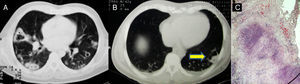

En octubre de 2010, el paciente requirió hospitalización por pérdida de peso e historia de 4 semanas con tos y hemoptisis, leucocitosis (11×103/μl), anemia (11,8g/dl), trombocitosis (603×103/μl), títulos altos de anticuerpos antiproteinasa 3 (130,7 U/ml) y elevación de proteína C reactiva (11,74mg/dl). La radiografía mostró múltiples nódulos bilaterales, algunos cavitados, y una gran cavitación en el lóbulo inferior derecho (fig. 2A); la tomografía ratificó los hallazgos, con paredes gruesas (más de 5mm) e irregulares de la cavitación mayor (fig. 2B). El PPD fue negativo. Se realizaron una broncoscopia y una biopsia con fórceps, en la que se demostró la presencia de bacilos ácido-alcohol-resistentes (fig. 2C); la reacción en cadena de la polimerasa informó de complejo Mycobacterium tuberculosis.